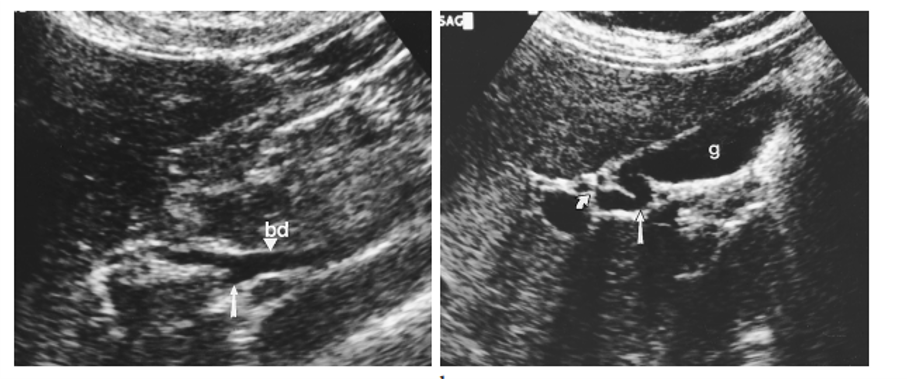

subvesicle bile duct –> can lead to persistent bile leak after cholecystectomy

what can lead to inadvertent common duct ligation in a cholecystectomy?

low insertion of the CBD